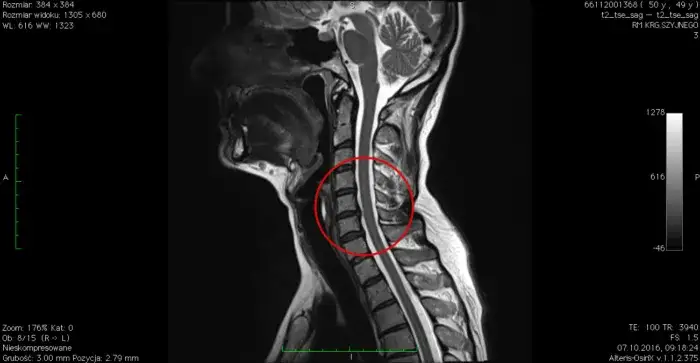

Poznaj objawy i metody leczenia przepukliny kręgosłupa szyjnego C6-C7. Dowiedz się, jak diagnozować i radzić sobie z bólem, drętwieniem oraz osłabieniem mięśni. Skuteczna pomoc w zasięgu ręki.